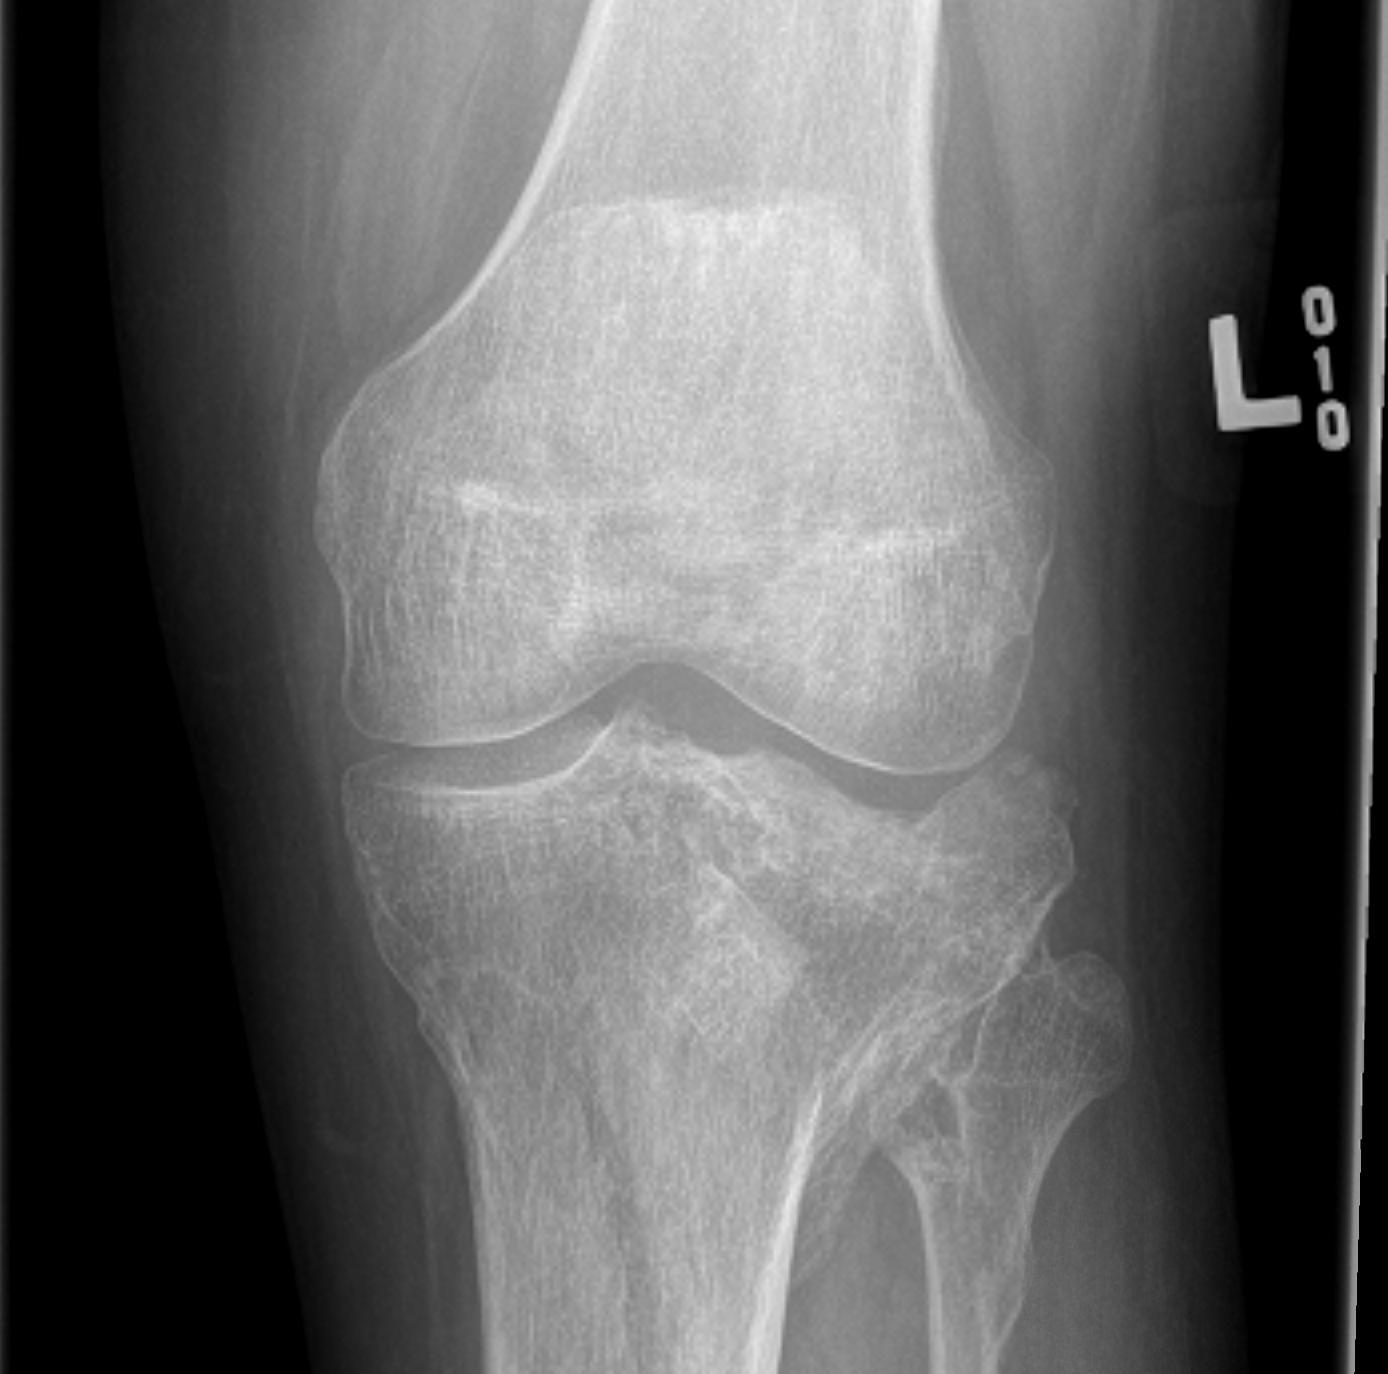

Cartilage defects

• Cartilage defects